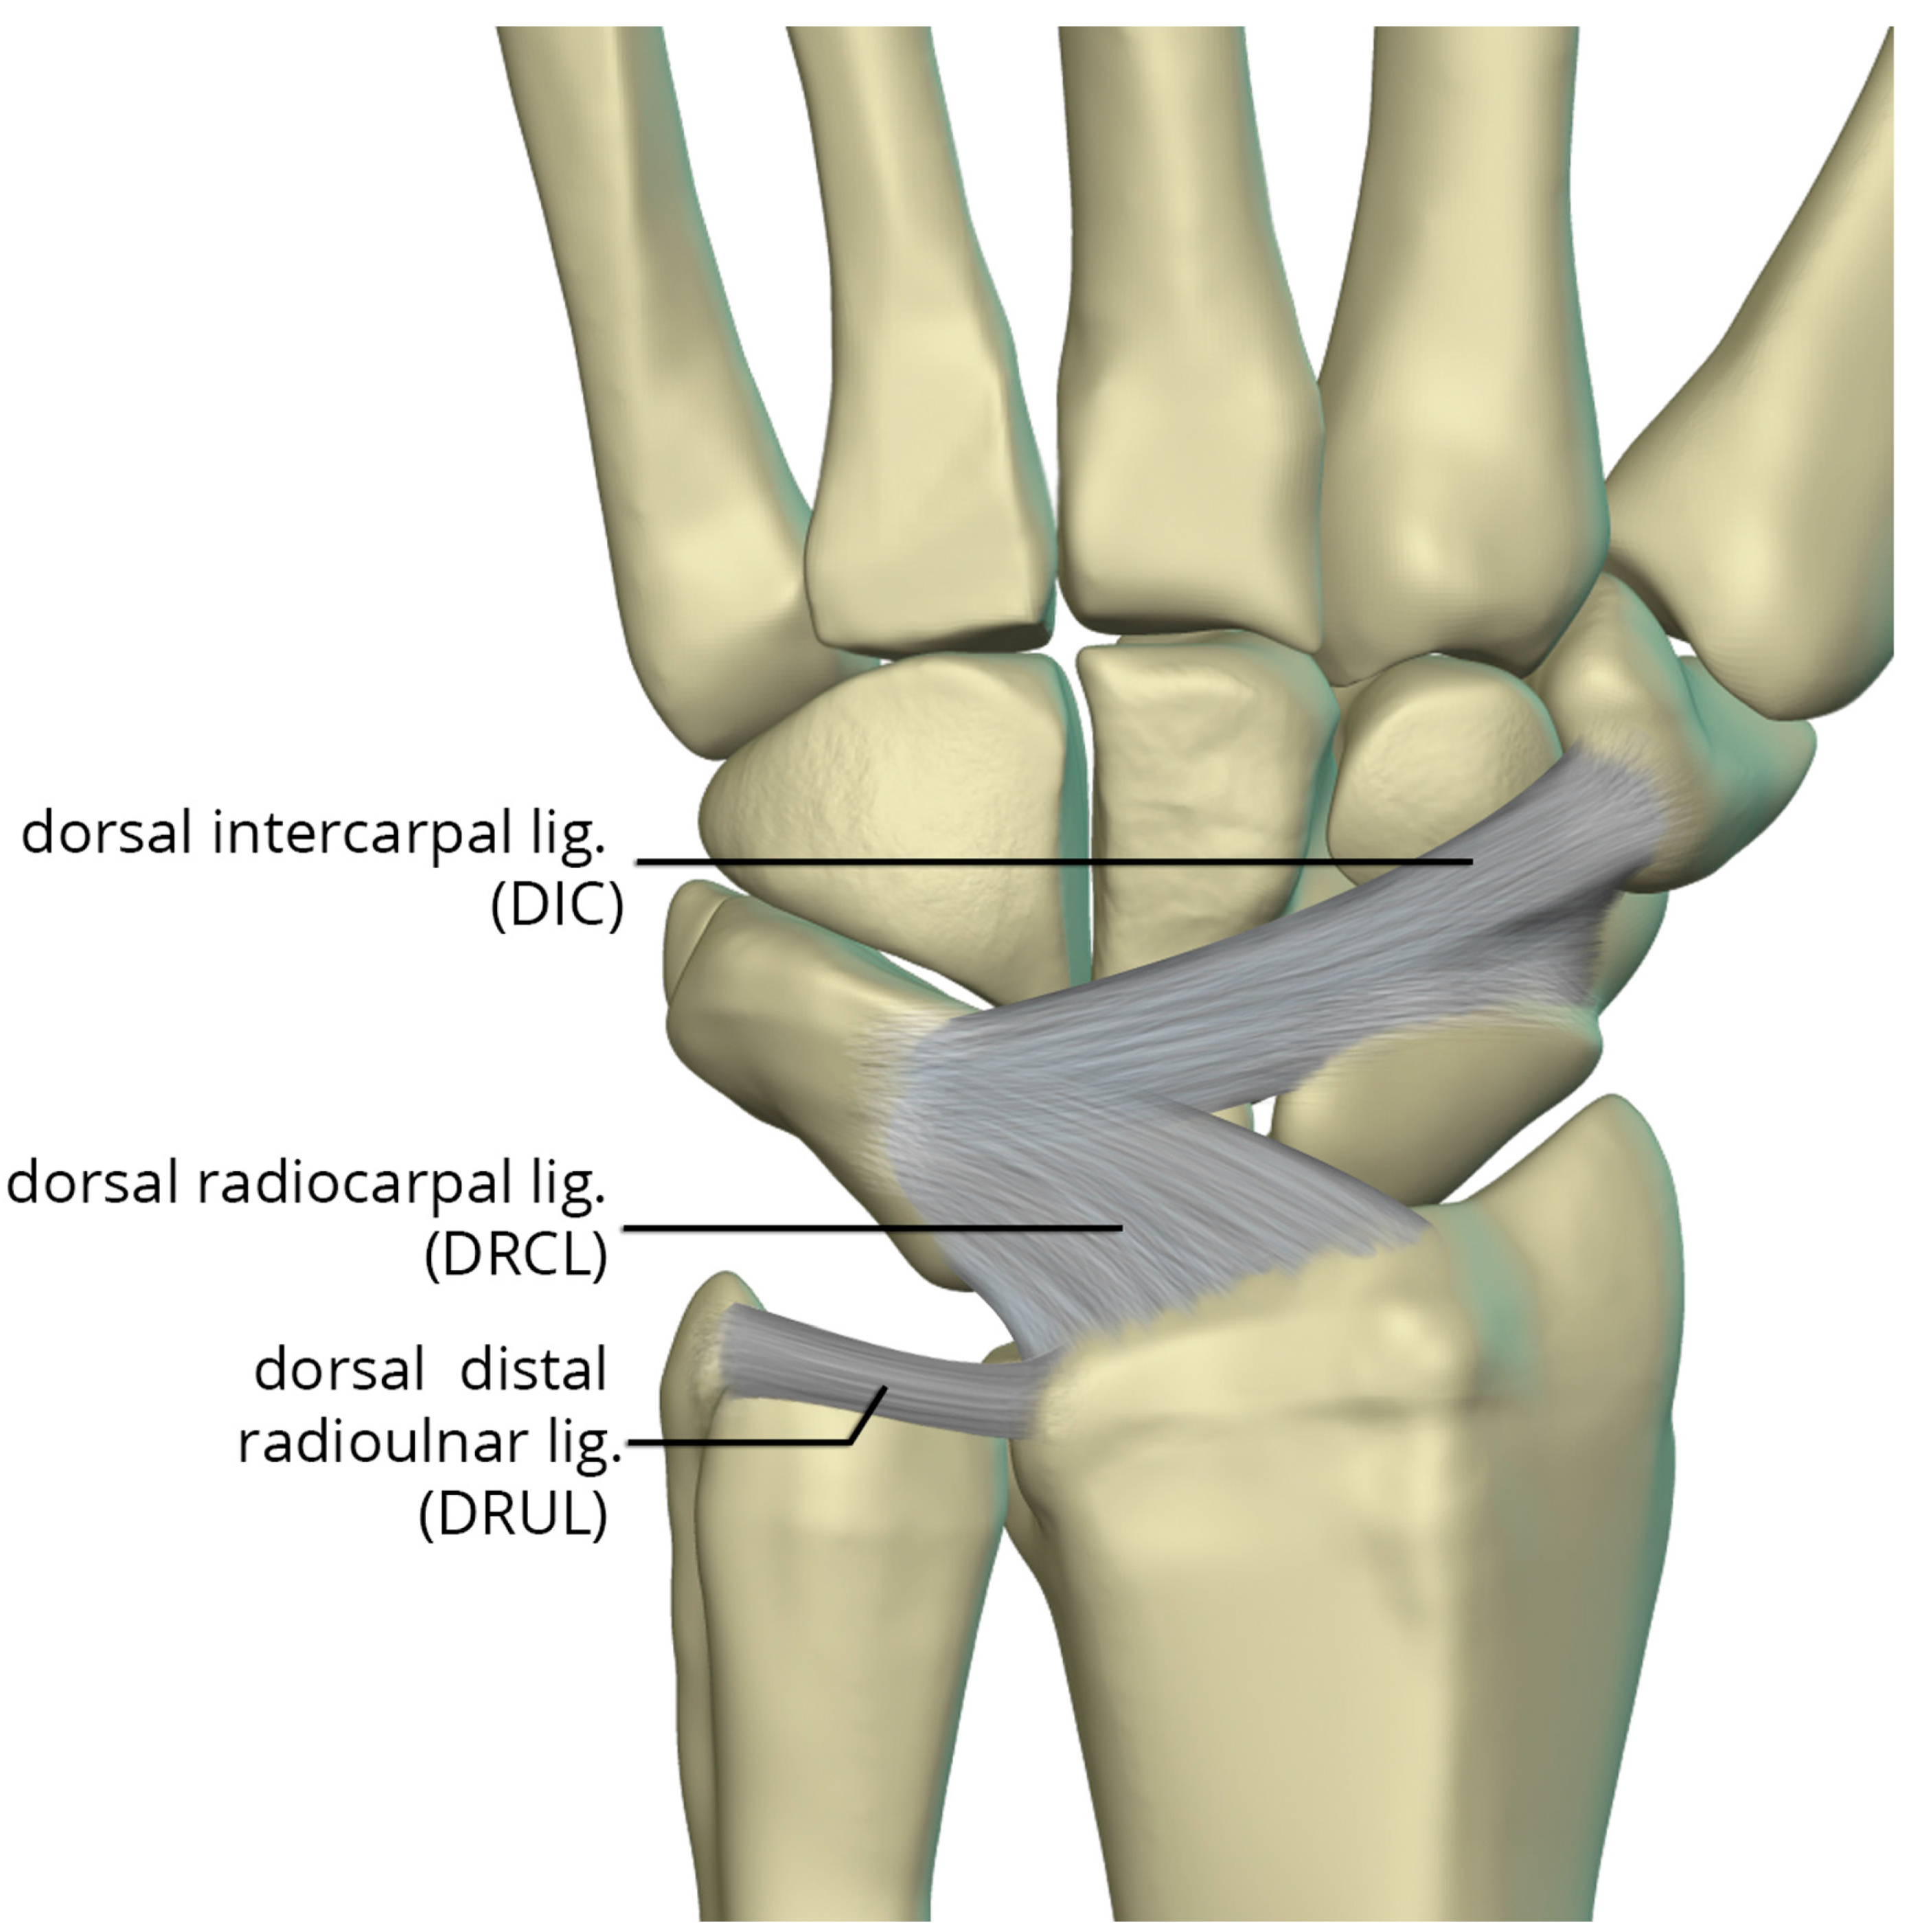

The dorsal capsular ligaments (Figure 25) include the dorsal radiocarpal ligament (DRCL) and dorsal intercarpal ligament (DIC). The dorsal radiocarpal ligament (DRCL) is also referred to as the dorsal radiotriquetral ligament [24]. The DRCL extends from dorsal rim of the radius, between Lister tubercle and the sigmoid notch, to the dorsal triquetrum. This ligament has fibers continuous with the 4th and 5th extensor compartment septa. Variants of this ligament include various additional bands, one of which may cover the dorsal aspect of the proximal scaphoid. The dorsal intercarpal ligament (DIC) is also sometimes referred to as the dorsal scaphotriquetral ligament due to its attachments. The DIC ligament extends from the dorsal ridge of the triquetrum to the dorsal groove of the scaphoid and proximal rim of the dorsal aspect of the trapezium. Along its course some fibers attach to the dorsal distal lunate. The DIC ligament may have 1 or 2 distinct fascicles, and sporadically has fibers extending to the trapezoid and capitate.

Figure 25. Illustration of the dorsal capsular ligaments: the dorsal radiocarpal ligament and dorsal intercarpal ligament.